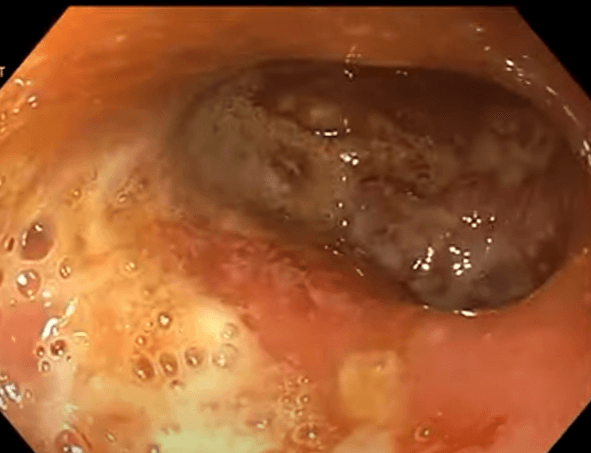

환자의 증상, 내시경과, CT 등 영상소견과 조직검사 소견을 종합하여 크론병으로 진단합니다.